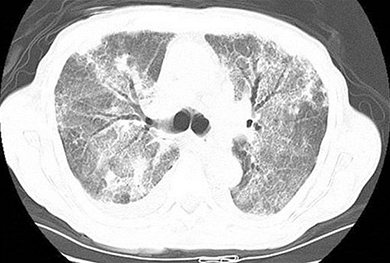

ARDS secondary to pulmonary coccidioidomycosis

This is a more severe form of the disease that can happen in a setting of high inoculum exposure or with accompanying immunosuppression and is often seen in patients with risk factors mentioned in the table. Patients are appearing ill, with mild to moderate respiratory distress, often with fever. Radiographic findings are usually consistent with multilobar diffuse infiltrates and adenopathy. Serious complications such as pleural effusions, empyema, and acute respiratory distress syndrome (ARDS) are often seen (1). Even with antifungal therapy, clinical improvement in such a disease may be slow, and patients often require significant and prolonged supportive care.

ARDS as a consequence of coccidioidal infection carries a very high mortality rate. An amphotericin B formulation is frequently used until clinical improvement occurs, followed by an azole for at least one year or longer. In selected individuals with ongoing immunosuppression or irreversible conditions, long-term maintenance therapy with an azole is suggested. The role of adjunctive corticosteroid therapy in coccidioidomycosis-associated ARDS has not been defined, and considerable debate exists between different clinicians.